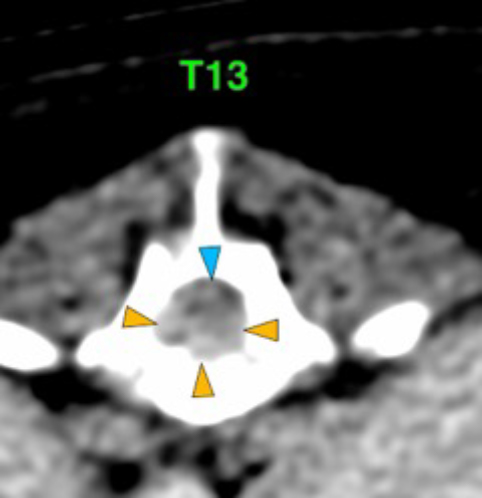

The osteolytic lesions have soft tissue attenuation that shows moderate and slightly heterogeneous post-contrast enhancement. In some of the vertebrae, the lesions cause lysis of the cortex and extend into the vertebral canal (orange arrows) causing variable degree of compression of the spinal cord and cauda equina (blue arrows). At the level of the vertebral bodies of T7, T8, T9 and T12 the lesions extend into the ventral and central aspect of the vertebral canal causing a mild compression of the spinal cord. At the level of T13, L1, L4 and L5 the lesions extend into the ventral and central aspect of the vertebral canal, causing moderate compression of the spinal cord. At the vertebral body of L6 the lesion extends into the ventral and central aspect of the vertebral canal, at the mid-aspect of L6, occupying approx. 90% of the diameter of the vertebral canal causing a severe compression of the cauda equina. At the level of L7, the lesion extends into the ventral and both lateral aspects of the vertebral canal, causing severe compression of the cauda equina.